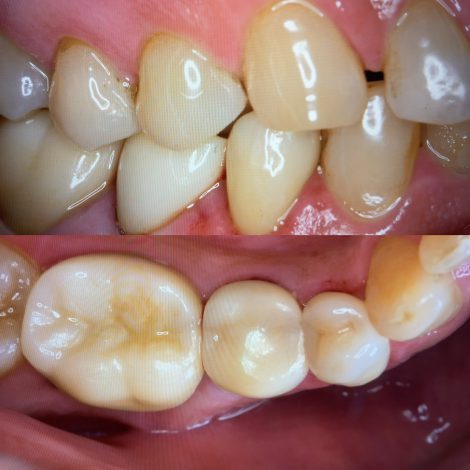

前歯のセラミック治療🦷

2021/06/26

こんにちは 最近前歯の治療のご相談をよく受けます 当院の治療の結果でご紹介いただくケースも増えてきたように感じます この時期は特に皆さんマスクをしていらっしゃるので、治療に関しては今が最適な時…